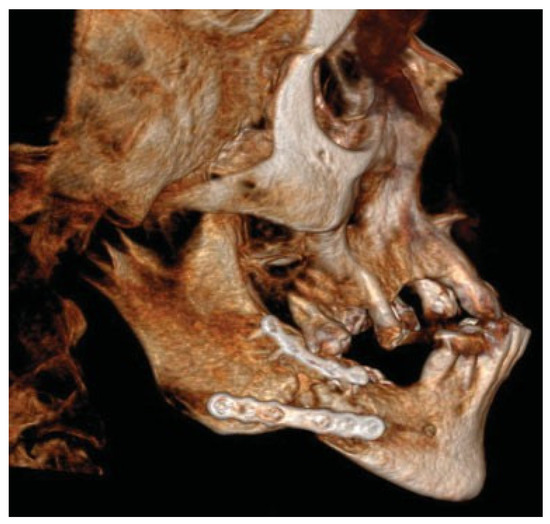

Figure 10.

After drilling holes with the help of the guide, the plate was easily attached in the planned position to the mandible.

Figure 11.

Immediate postoperative situation captured with CBCT.